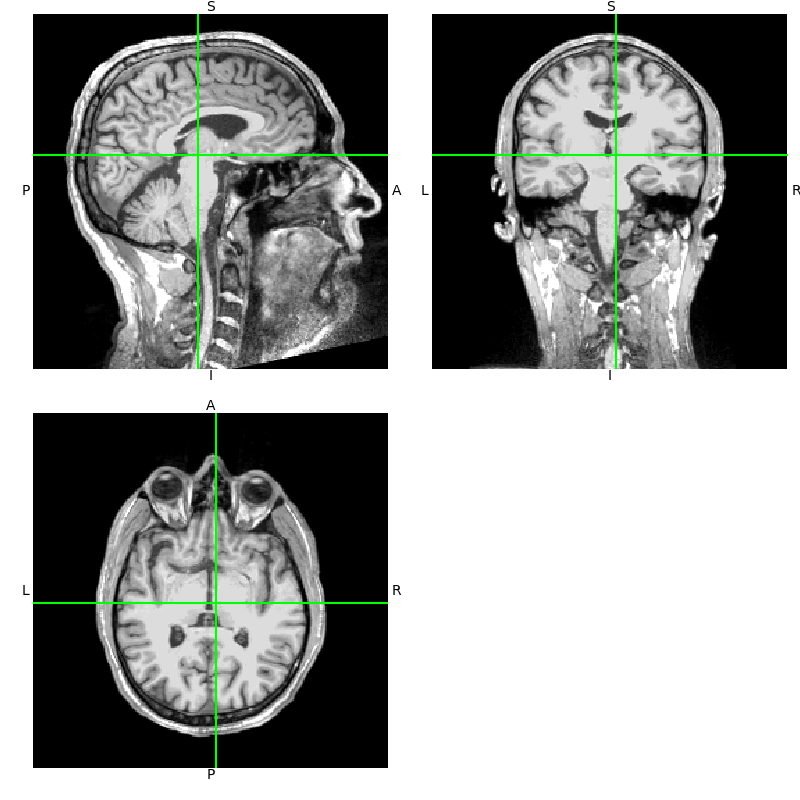

Let’s start out by looking at the sample subject MRI. Following standard

FreeSurfer convention, we look at T1.mgz, which gets created from the

original MRI sample/mri/orig/001.mgz when you run the FreeSurfer

command recon-all.

Here we use nibabel to load the T1 image, and the resulting object’s

orthoview() method to view it.

Notice that the axes in the

orthoview() figure are labeled

L-R, S-I, and P-A. These reflect the standard RAS (right-anterior-superior)

coordinate system that is widely used in MRI imaging. If you are unfamiliar

with RAS coordinates, see the excellent nibabel tutorial

Coordinate systems and affines.